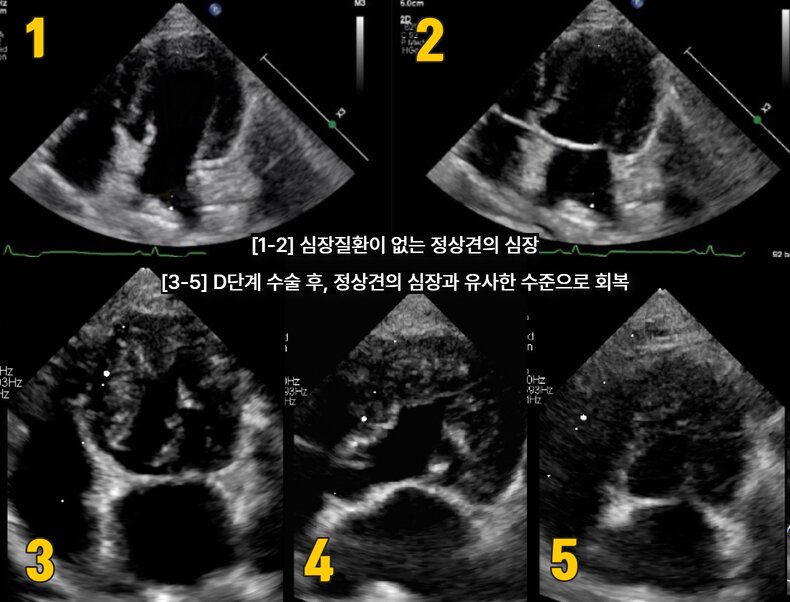

본문 이미지 - D단계 수술 후, 정산견의 심장과 유사한 수준으로 회복된 반려견의 심장초음파(넬동물의료센터 제공) ⓒ 뉴스1

D단계 수술 후, 정산견의 심장과 유사한 수준으로 회복된 반려견의 심장초음파(넬동물의료센터 제공) ⓒ 뉴스1